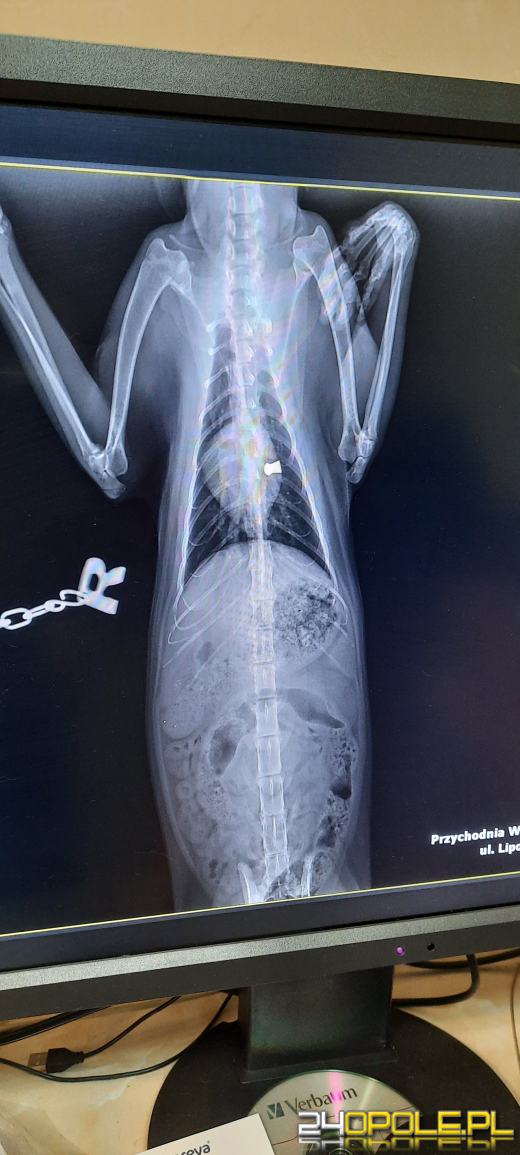

Do naszej redakcji zgłosił się pan Daniel, który w czwartek 18 maja znalazł kota z raną postrzałową. Dzięki szybkiej reakcji mieszkańca Pucnika udało się wyciągnąć śrut z klatki piersiowej, jednak zwierzę jest w ciężkim stanie. Mieszkaniec Pucnika obawia się, że proceder może się powtórzyć.